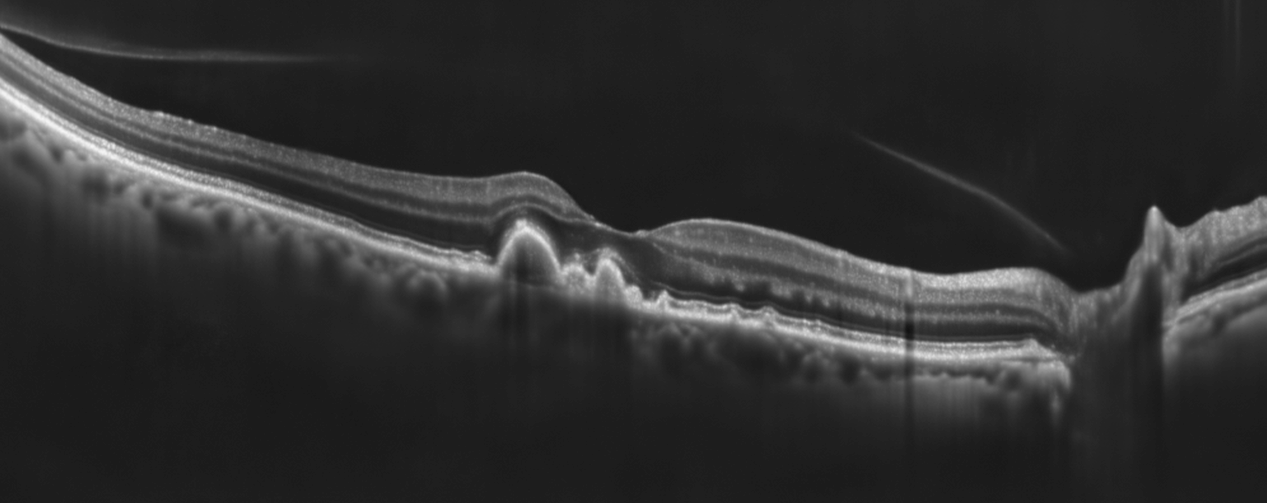

Netthinne uten druser til venstre (gjengitt med tillatelse)

Netthinne med druser til høyre (gjengitt med tillatelse)